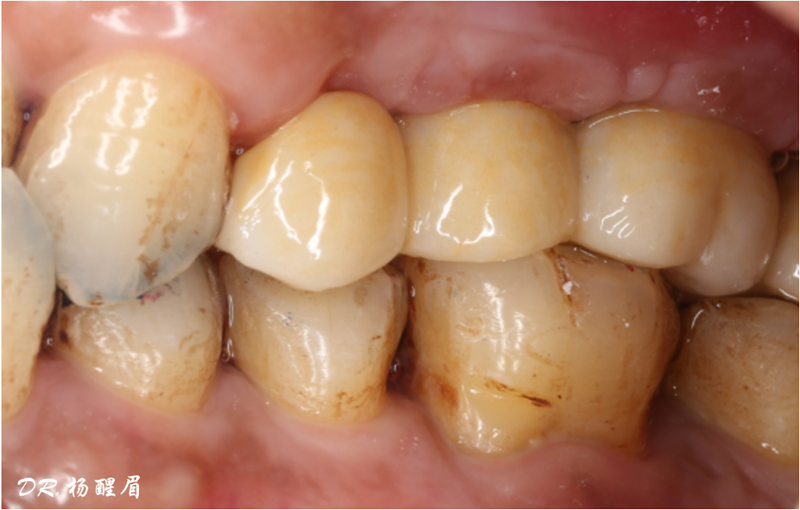

修復完成

®多顆植體位點及角度的精確性,確保后期修復方案順利完成,也使患者能在使用過程中承受最佳的咬合力

®袖口形態(tài)

®基樁形態(tài)